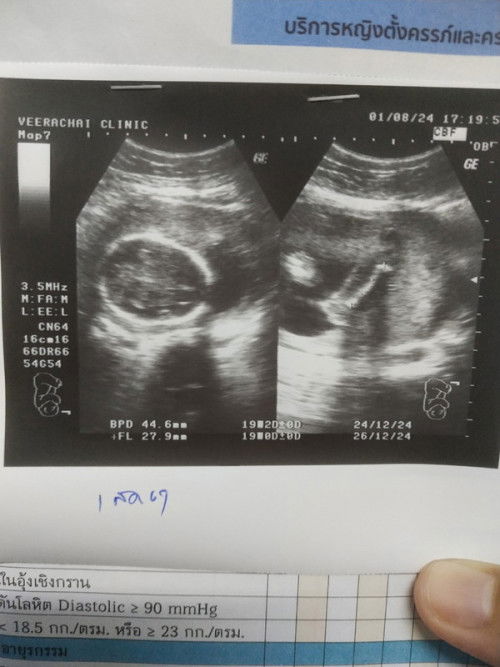

แอบแตกแล้วจ้าาา กำหนด 25 ธันวา น้องเลือก 14 ธันวา

38W3D วันที่ 13 ปวดท้องไปโรงบาล 18:00 มดลูกเปิด 2 ซม. หมอให้กลับบ้านดูอาการ ตี 1:14 น้ำคร่ำแตกนิดเดียว ปวดท้องทนได้ ตี 1:41 น้ำคร่ำแตกรอบ 2 ไหลเต็มพื้น เริ่มปวดท้องหนักขึ้น จนตี 4:30 ไปหาหมอเพราะปวดจนตัวแข็ง ไปถึงหมดลูกเปิด 9 ซม. หมอเตรียมทำคลอดแทบไม่ทัน 😆 แตกตอนตี 5:47 คลอดธรรมชาติ บล็อคหลังไม่ทันจ้า น้องมีภาวะหายใจเร็ว,หัวใจเต้นเร็ว,สายสะดือพันคอ 1 รอบ ตอนคลอดออกมาสายสะดือขาดทำให้เลือดแม่ผสมกับลูก ได้เข้าเครื่องช่วยหายใจ 3 วัน กลับมาแข็งแรงแล้วจ้า #ขอบคุณสำหรับคำคอมเม้นล่วงหน้าค่ะ #ขอบคุณล่วงหน้าสำหรับความคิดเห็นค่ะ #คุณแม่มือใหม่